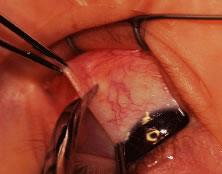

SCLERAL PERFORATION

Recognized and unrecognized scleral perforation will occur. Reattachment of the muscle to the globe requires passing a needle within the sclera. The scleral coat of the globe is thinnest just posterior to the insertion of the rectus muscles. If the sclera becomes dry, it will thin further, and the blue color of the underlying uveal tissue will be visible. Needles with specially designed spatula tips are used to draw the sutures through the scleral tissue. Adequate illumination and magnification will facilitate this procedure. If the operation is prolonged, periodic wetting of the cornea and sclera with saline or a balanced salt solution will reduce thinning resulting from desiccation. In addition, adequate exposure and stabilization of the globe will reduce this complication. Scleral perforation also can occur when the needle is in the sclera and the surgeon attempts to lift the tip of the needle by placing torque on the needle with the needle holder (see Fig. 36). The fine-wire needles will bend, and, when the needle is released, the tip is directed posterior or into the sclera. Unexpected movement of the patient also may cause perforation of the globe (Fig. 78).

Fig. 78. This patient unexpectedly moved when the muscle was being cut from its insertion. The sclera had a small tear that was closed with two 8-0 silk sutures.